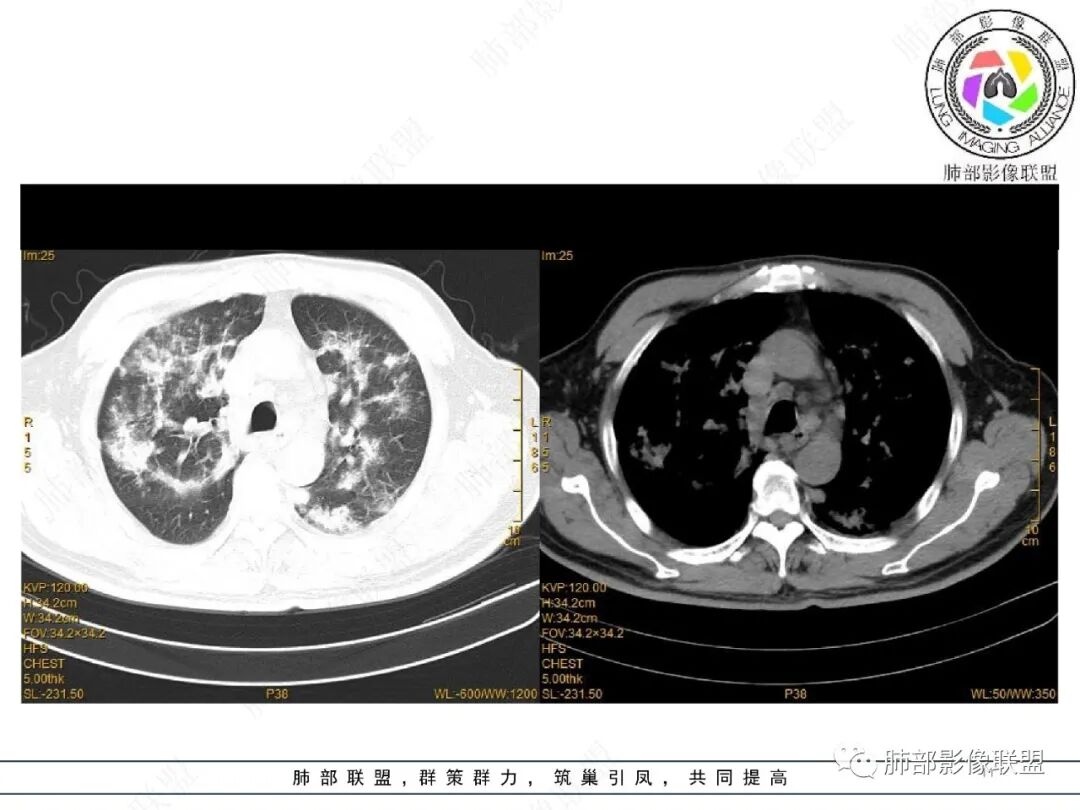

2022.2.17CT显示两肺中内带多发结节影、斑片影、条索影,部分病灶侧向融合与胸膜平行。部分病灶沿着支气管血管束分布、其内支气管稍扩张。部分病灶呈反晕征。大部分病灶边界显示清晰,部分病灶周围可见边界不清的GGO。2022.4.12CT显示两肺中内带多发结节影、条索状、条带状高密度影,边界收缩平直凹陷,大部分病灶沿着支气管血管束分布,亦有位于胸膜下侧向融合与胸膜平行的病灶。总体与第一次CT对比两肺病灶明显吸收。

3、病例小结:

老年男性,两肺多发病灶,整体呈OP样改变,至于是原发性还是继发性的OP,需要临床鉴别。此病例穿刺结果是隐球菌。该病例CT上缺乏隐球菌典型的“在那遥远的胸膜下,多个蘑菇兄弟,可以侧向融合呈长串状与胸膜平行”影像表现,更多是OP样改变,仅凭临床表现或影像资料诊断隐球菌难度比较大。当然也不除外二元论,导致隐球菌的影像表现被掩盖。